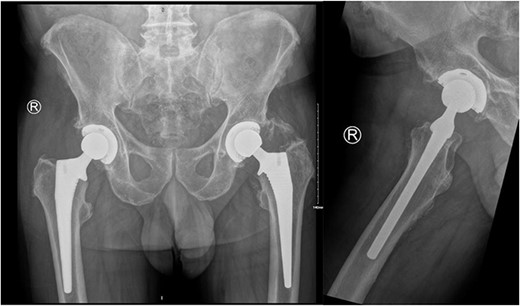

On examination, he had an antalgic gait and his range of motion was globally restricted due to pain. There was significant swelling and erythema over the operative site. His blood investigations demonstrated that his inflammatory markers were mildly elevated: white cell count (WCC) 8.5, CRP 14. X-rays showed satisfactory position of the implants (Fig. 2).

AP pelvis and lateral right hip radiographs 6 weeks post primary right THR when our patient presented with clinical signs of PJI. The implants were in a satisfactory position.